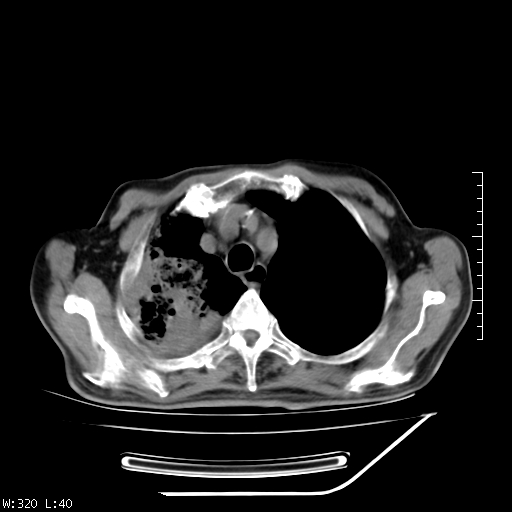

标题: CT23994:男、72、咳嗽、气短两月余,近来消瘦。 [打印本页]

标题: CT23994:男、72、咳嗽、气短两月余,近来消瘦。

tb可能性大(双肺均可见片状密度增高灶,其内可见低密度空洞)。

右上肺大片状密度增高影,与胸膜关系密切,内见低密度透亮影,胸膜下可见三角形不张影,左下肺沿支气管走形结节影,纵膈内淋巴结显示。考虑结核并疤痕性不张可能性大,建议穿刺活检,排除肺泡癌。